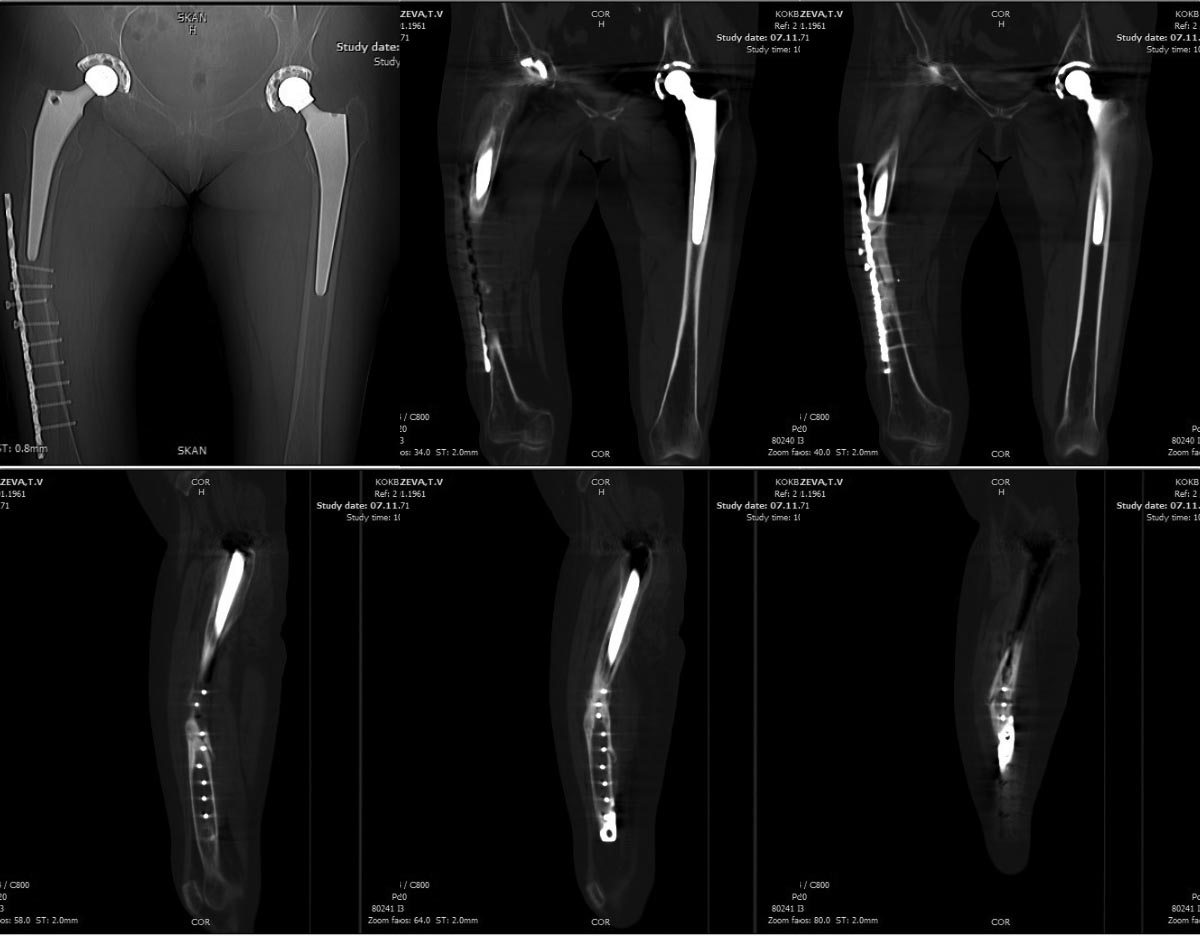

Перипротезный перелом

Пациентка К., находясь у родственников в гостях 26.10.2014. - оступилась по неосторожности при ходьбе по лестнице (пациентка утверждает, что падения на конечность не было, именно оступилась). Ранее в марте 2014 года травма бытовая - упала дома по неосторожности, оперирована в городе Н. в апреле 2014 года - остеосинтез правого бедра пластиной DCP, беспокоили постоянные боли при нагрузке в с\3 правого бедра.

Тотальное эндопротезирование правого т/бедренного сустава в 2013г, левого т/бедренного сустава в 2012г.

Клинически: патологической подвижности нет. Передвигается с костылями без опоры не правую ногу. Боль при осевой нагрузке.

Определили данное повреждение как слабоконсолидированный со смещением перипротезный перелом с\3 правой бедренной кости тип С (по классификации Vancouver). Миграция импланта.

Рассматриваем несколько варинтов лечения:

1. Удаление пластины, остеосинтез минимально инвазвно штифтом с блокированием по технологии представленной А.Н. Челноковым

2. Удаление ножки эндопротеза (хотя на мой взглад она стабильна, поправьте меня если ошибаюсь) ревизионное протезирование ножкой Вагнера.

МСКТ прилагаются